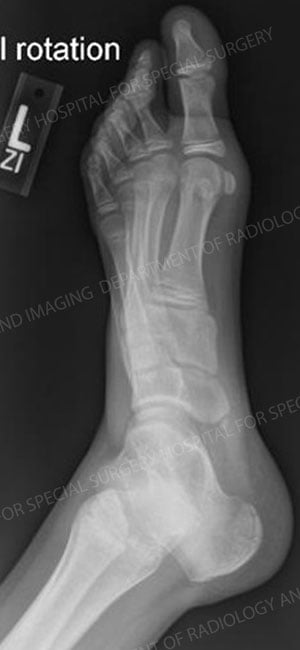

Accessory navicular describes the presence of an extra bone growth center on the inside of the navicular and within the posterial tibial tendon that attaches to the navicular. The primary symptom from this additional bony prominence is pain and tenderness.

X-ray image of the left foot with an accessory navicular.

Enlarged view of the affected area. The red arrow indicates the accessory navicular.

This congenital defect (present at birth) is thought to occur during development when the bone is calcifying. Because this accessory portion of the bone and the navicular never quite grow together, it is believed that, over time, the excessive motion between the two bones results in pain.

The initial treatment approach for accessory navicular is non-operative. An orthotic may be recommended or the patient may undergo a brief period of casting to rest the foot. For chronic pain, however, the orthopedic surgeon removes the extra bone, a relatively simple surgery with a brief rehabilitation period and a very good success rate.